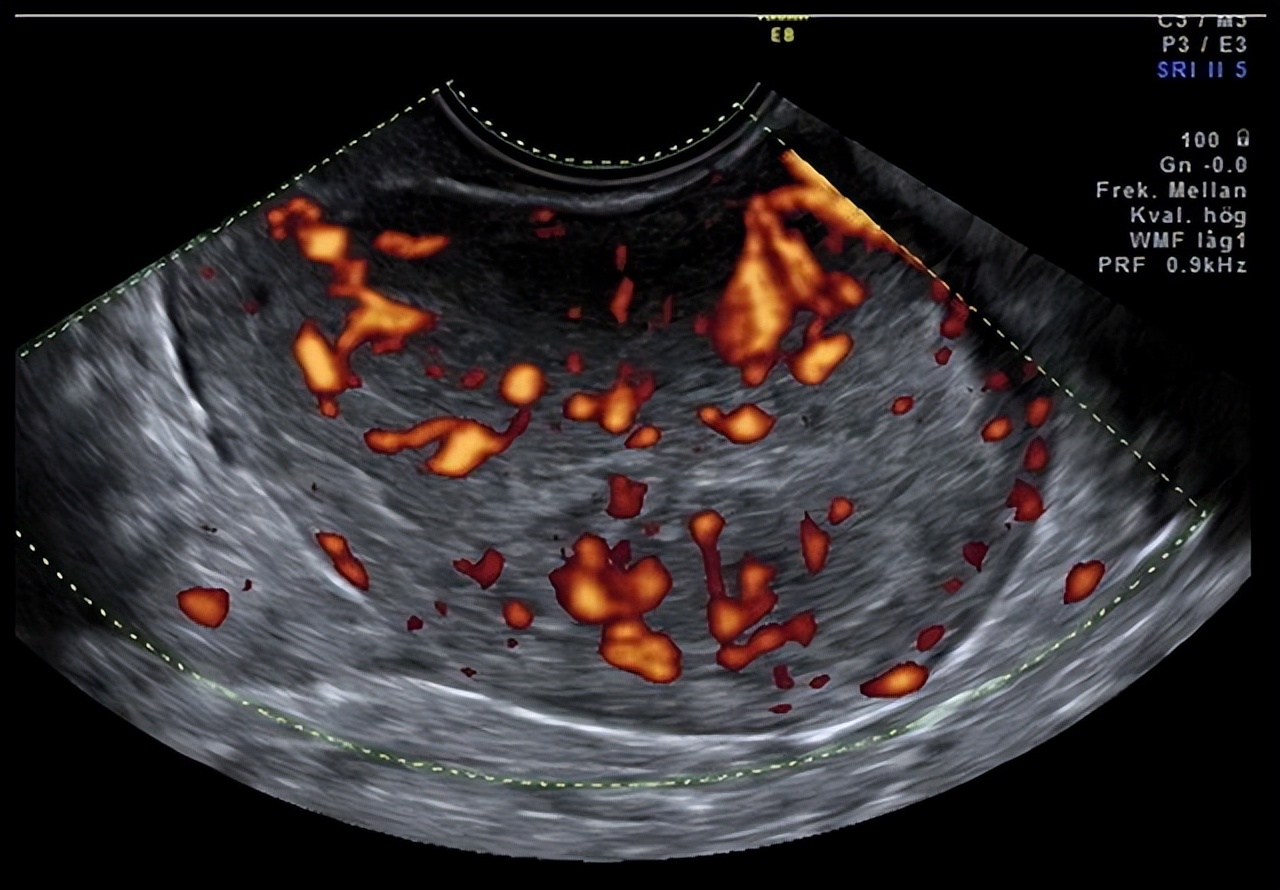

听完他们漫长而艰辛的求子之路,小钟医生为他们感到辛酸,但这个阴道出血不简单,遂常规开子宫附件彩超检查。

检查结果提示,子宫内膜厚度34 mm!正常来说,健康女人的子宫内膜厚度达到12 mm即可来月经。

而张姐刮宫后子宫内膜仍如此之厚,不必怀疑了,子宫内膜已经存在病变了。